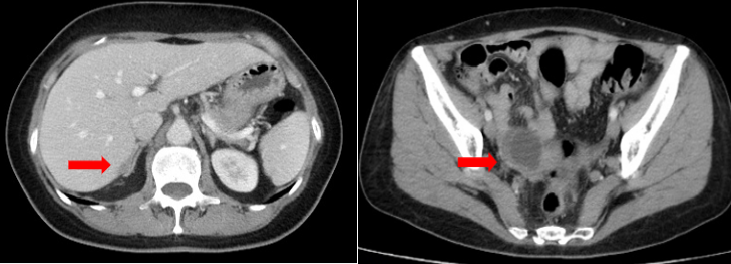

患者2018年5月出现无明显诱因全腹钝痛,当地医院就诊,B超检查示“双侧附件囊实性包块,性质待查”。遂至我院就诊,查体,生命体征平稳,一般状况良好,二便基本正常。专科查体:右附件区扪及约4 cm包块,质中,活动欠佳,无压痛,左附件区增厚,无压痛,移动性音可疑阳性。CT检查提示:右附件3.8×3.3 cm囊实性占位,腹膜增厚,肝肾间隙、脾肾间隙旁、大网膜及左侧结肠旁沟腹膜增厚,局部见小结节影,腹盆腔少量积液,考虑肿瘤种植转移可能(图1)。肿瘤标记物血CA125 2833.503 U/ml。行腹腔穿刺,抽出血性腹水200 ml,送病检,查见腺癌细胞。CT的Suidan评分>3分。

图1. 入院时CT检查结果